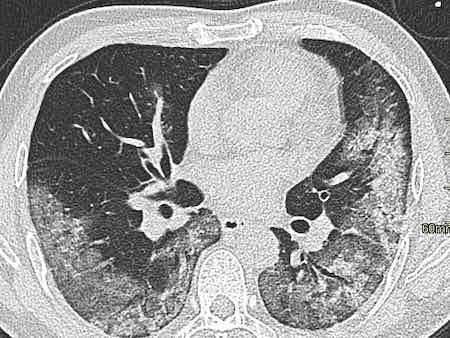

Covid CT Pattern

These are the latest Covid CT Pattern images from around the world.